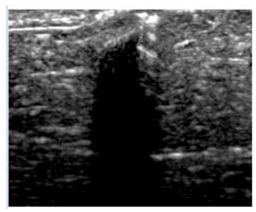

3.3. B-Mode Images

3.5. Echogenicity

4.1. Ultrasonography and Aerogel Dimensional Analyis

| Aerogel Type | US Image | Normalized Intensity Map | 3D Intensity Map | |

|---|---|---|---|---|

| 1 | Muscle |  |  |  |

| 2 | X-silica |  |  |  |

| 3 | X-silica-La2O2S:Eu |  |  |  |

| 4 | SMPU-Mix-14 |  |  |  |

| 5 | SMPU-Mix-18 |  |  |  |

| 6 | BRF-CA |  |  |  |

| 7 | ARF-CA |  |  |  |

| 8 | X-Ca-Alg-2 |  |  |  |

| 9 | X-Ca-Alg-1 |  |  |  |